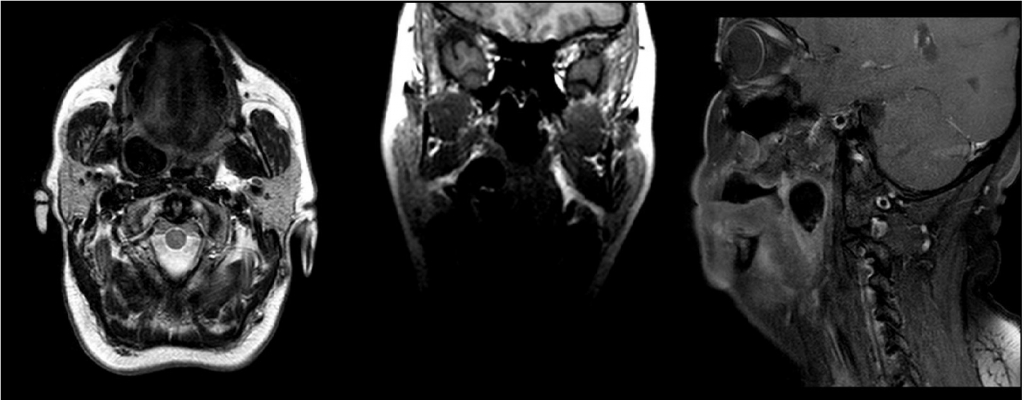

AbstractTonsilloliths are calcified masses which present in tonsillary cripts. They often contain calcium carbonate, oxalate, other magnesium salts, and ammonium radicals. They may cause complaints such as halitosis, difficulty swallowing, sore throat, and referred otalgia related to their size and location. It may go asymptomatic and may detect a submucosal or intratonsiller mass in routine controls. The diagnosis can be made clinically, as well as through direct radiography, CT, and MR imaging. In treatment, excision of tonsillolith is feasible, and in some cases, releated tonsillectomy can also be done. In this case, a giant tonsillolith located in the right palatine tonsil lodge and causing complaints of sore throat and dysphagia is presented.IntroductionTonsil stones are calcified formations that develop in the crypts of the tonsils. These precipitates frequently comprise calcium carbonate, oxalate, additional magnesium salts, and ammonium radicals [1].The precise mechanisms underlying these formations remain to be fully elucidated. The prevailing hypothesis suggests that caseous material accumulates in the tonsil crypts, where it combines with filaments of bacteria, such as Leptothrix buccalis, which are associated with chronic tonsillitis [1, 2]. Depending on the size and location, the condition may present with symptoms including halitosis, dysphagia, sore throat and referred otalgia [2, 3]. It is important to note that these lesions may be asymptomatic and, as such, may be identified during routine controls as an intra-tonsillar or submucosal mass. Although it can also be observed in children, it is most frequently observed in adults, with an average age of 50 years [2]. A clinical examination may reveal the presence of the condition in the tonsillar crypt, or it may be palpated as a hard mass in the tonsillar tissue. The diagnosis can be made clinically, or by means of direct radiography. CT and MR imaging can also be used. In the treatment, the removal of the stone, along with the removal of the associated tonsil in some cases, may be performed. The presented case involves a giant tonsillolith with unilateral localization and a preliminary diagnosis of malignancy. The etiology of this condition is discussed in the context of existing literature on the subject. Case ReportA 51-year-old female patient attended the outpatient clinic and presented with symptoms of a sore throat on the right side of her neck and discomfort during swallowing. These symptoms had been gradually worsening over the course of the past six months. A thorough examination of the oral cavity of the patient revealed the presence of swelling in the right tonsillar lobe and the right lateral part of the soft palate. Additionally, the right palatine tonsil exhibited signs of swelling and medial pushing. Bimanual palpation revealed that the right palatine tonsil was large and firm in consistency. Magnetic resonance imaging (MRI) was performed at a different healthcare facility with prediagnoses of malignancy and tonsil stones. A 2x1 cm hypointense area with sharp borders to surrounding tissues and no contrast enhancement was observed on MRI imaging in the right palatine tonsil fossa. (Figure 1).